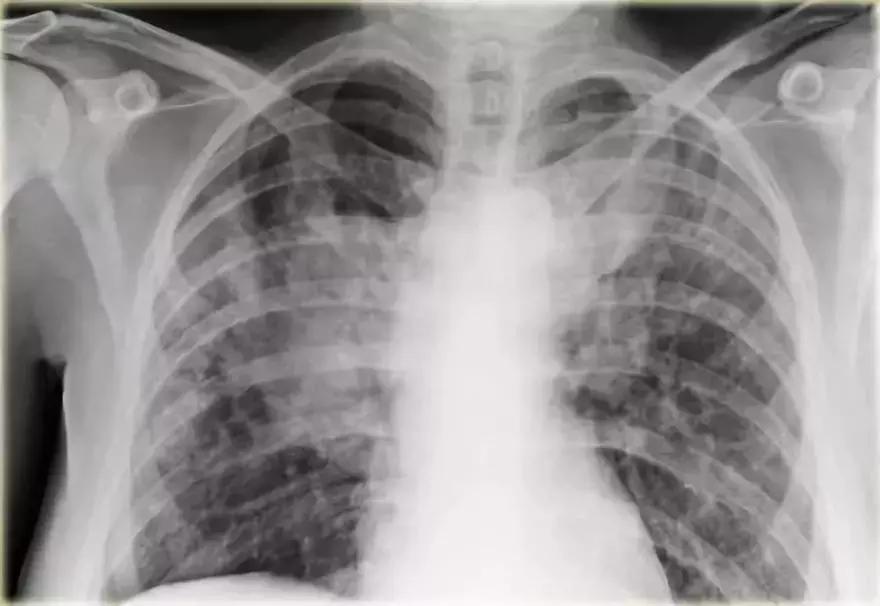

支气管肺泡癌弥漫性实变

➢ 胸部X线显示左肺出现“白肺”弥漫性实变,伴有空气-支气管征

➢ 患者是进行性实变的慢性疾病

➢ 患者左肺持续实变,最终扩散到右肺

最终诊断:支气管肺泡癌

图12 支气管肺泡癌弥漫性实变